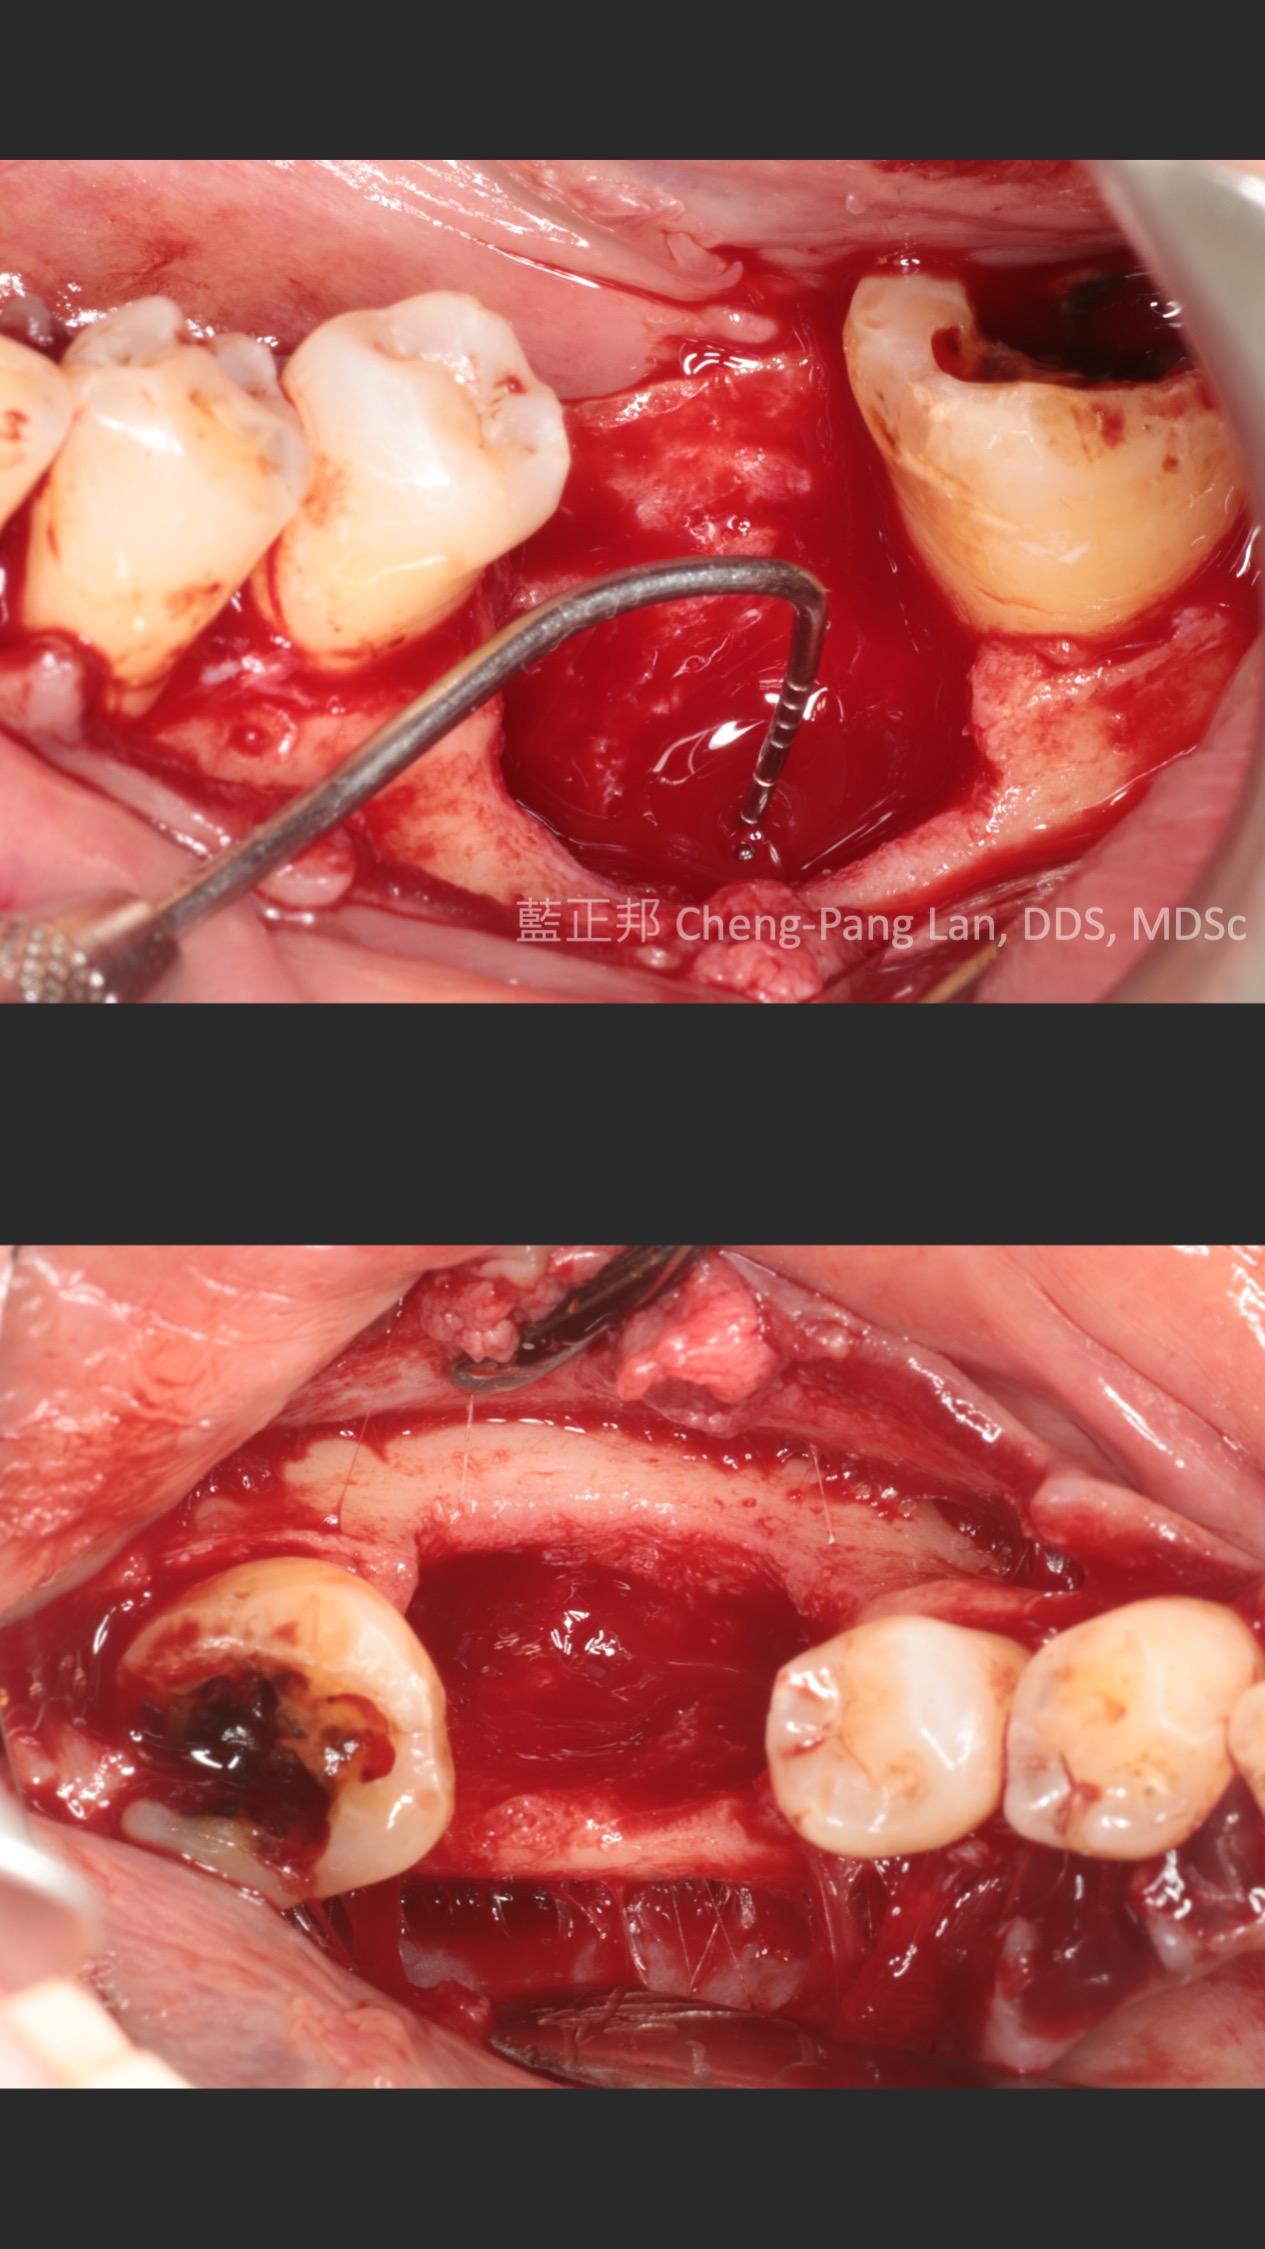

這個案例,最早沒把握能救回來,但是做完非手術治療,發現恢復非常好。

於是大膽地請矯正與假牙專科醫師一起幫忙完成。其實病人本身也同意,若途中狀況不好,還是得拔除。我知道這種案例,其實對其他專科來說,可能是有壓力的,不容易處理,也是難症。

好佳在,兩位神隊友都完成了,非常感謝合作專科的信任,還有,病患六年來維持得非常好,目前囊袋正常、零出血、零發炎。

回頭看,一開始就拔掉牙齒,改走其他路線,或許也可以,每位醫師選擇的或許不一樣,並沒有標準答案。

但是,能幫病患留下自己的牙齒,真的是很開心的一件事~~